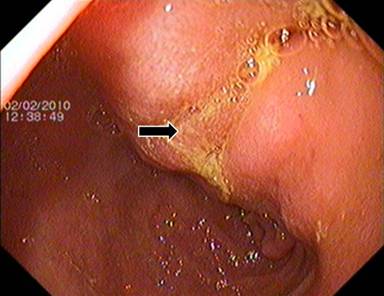

After initial stabilization with analgesics, hydration and parenteral nutritional support, a CECT abdomen was done for better characterization of pancreatic head mass. It revealed a 6x5 cm conglomerated lymph node mass in the peripancreatic and periportal region encasing the hepatic artery with preservation of fat plane between the mass and pancreatic head. There was circumferential wall thickening of body and antrum of stomach (14 mm) with luminal narrowing (Figure 1). CA 19-9 was normal. Upper gastrointestinal endoscopy showed thickened folds in the body of stomach with antral nodularity and a few superficial ulcers. First part of duodenum showed a 2x1 cm ulcer on the postero-superior wall (Figure 2).

Figure 2. Upper gastrointestinal endoscopy showing thickened gastric folds in distal body (black arrow). |